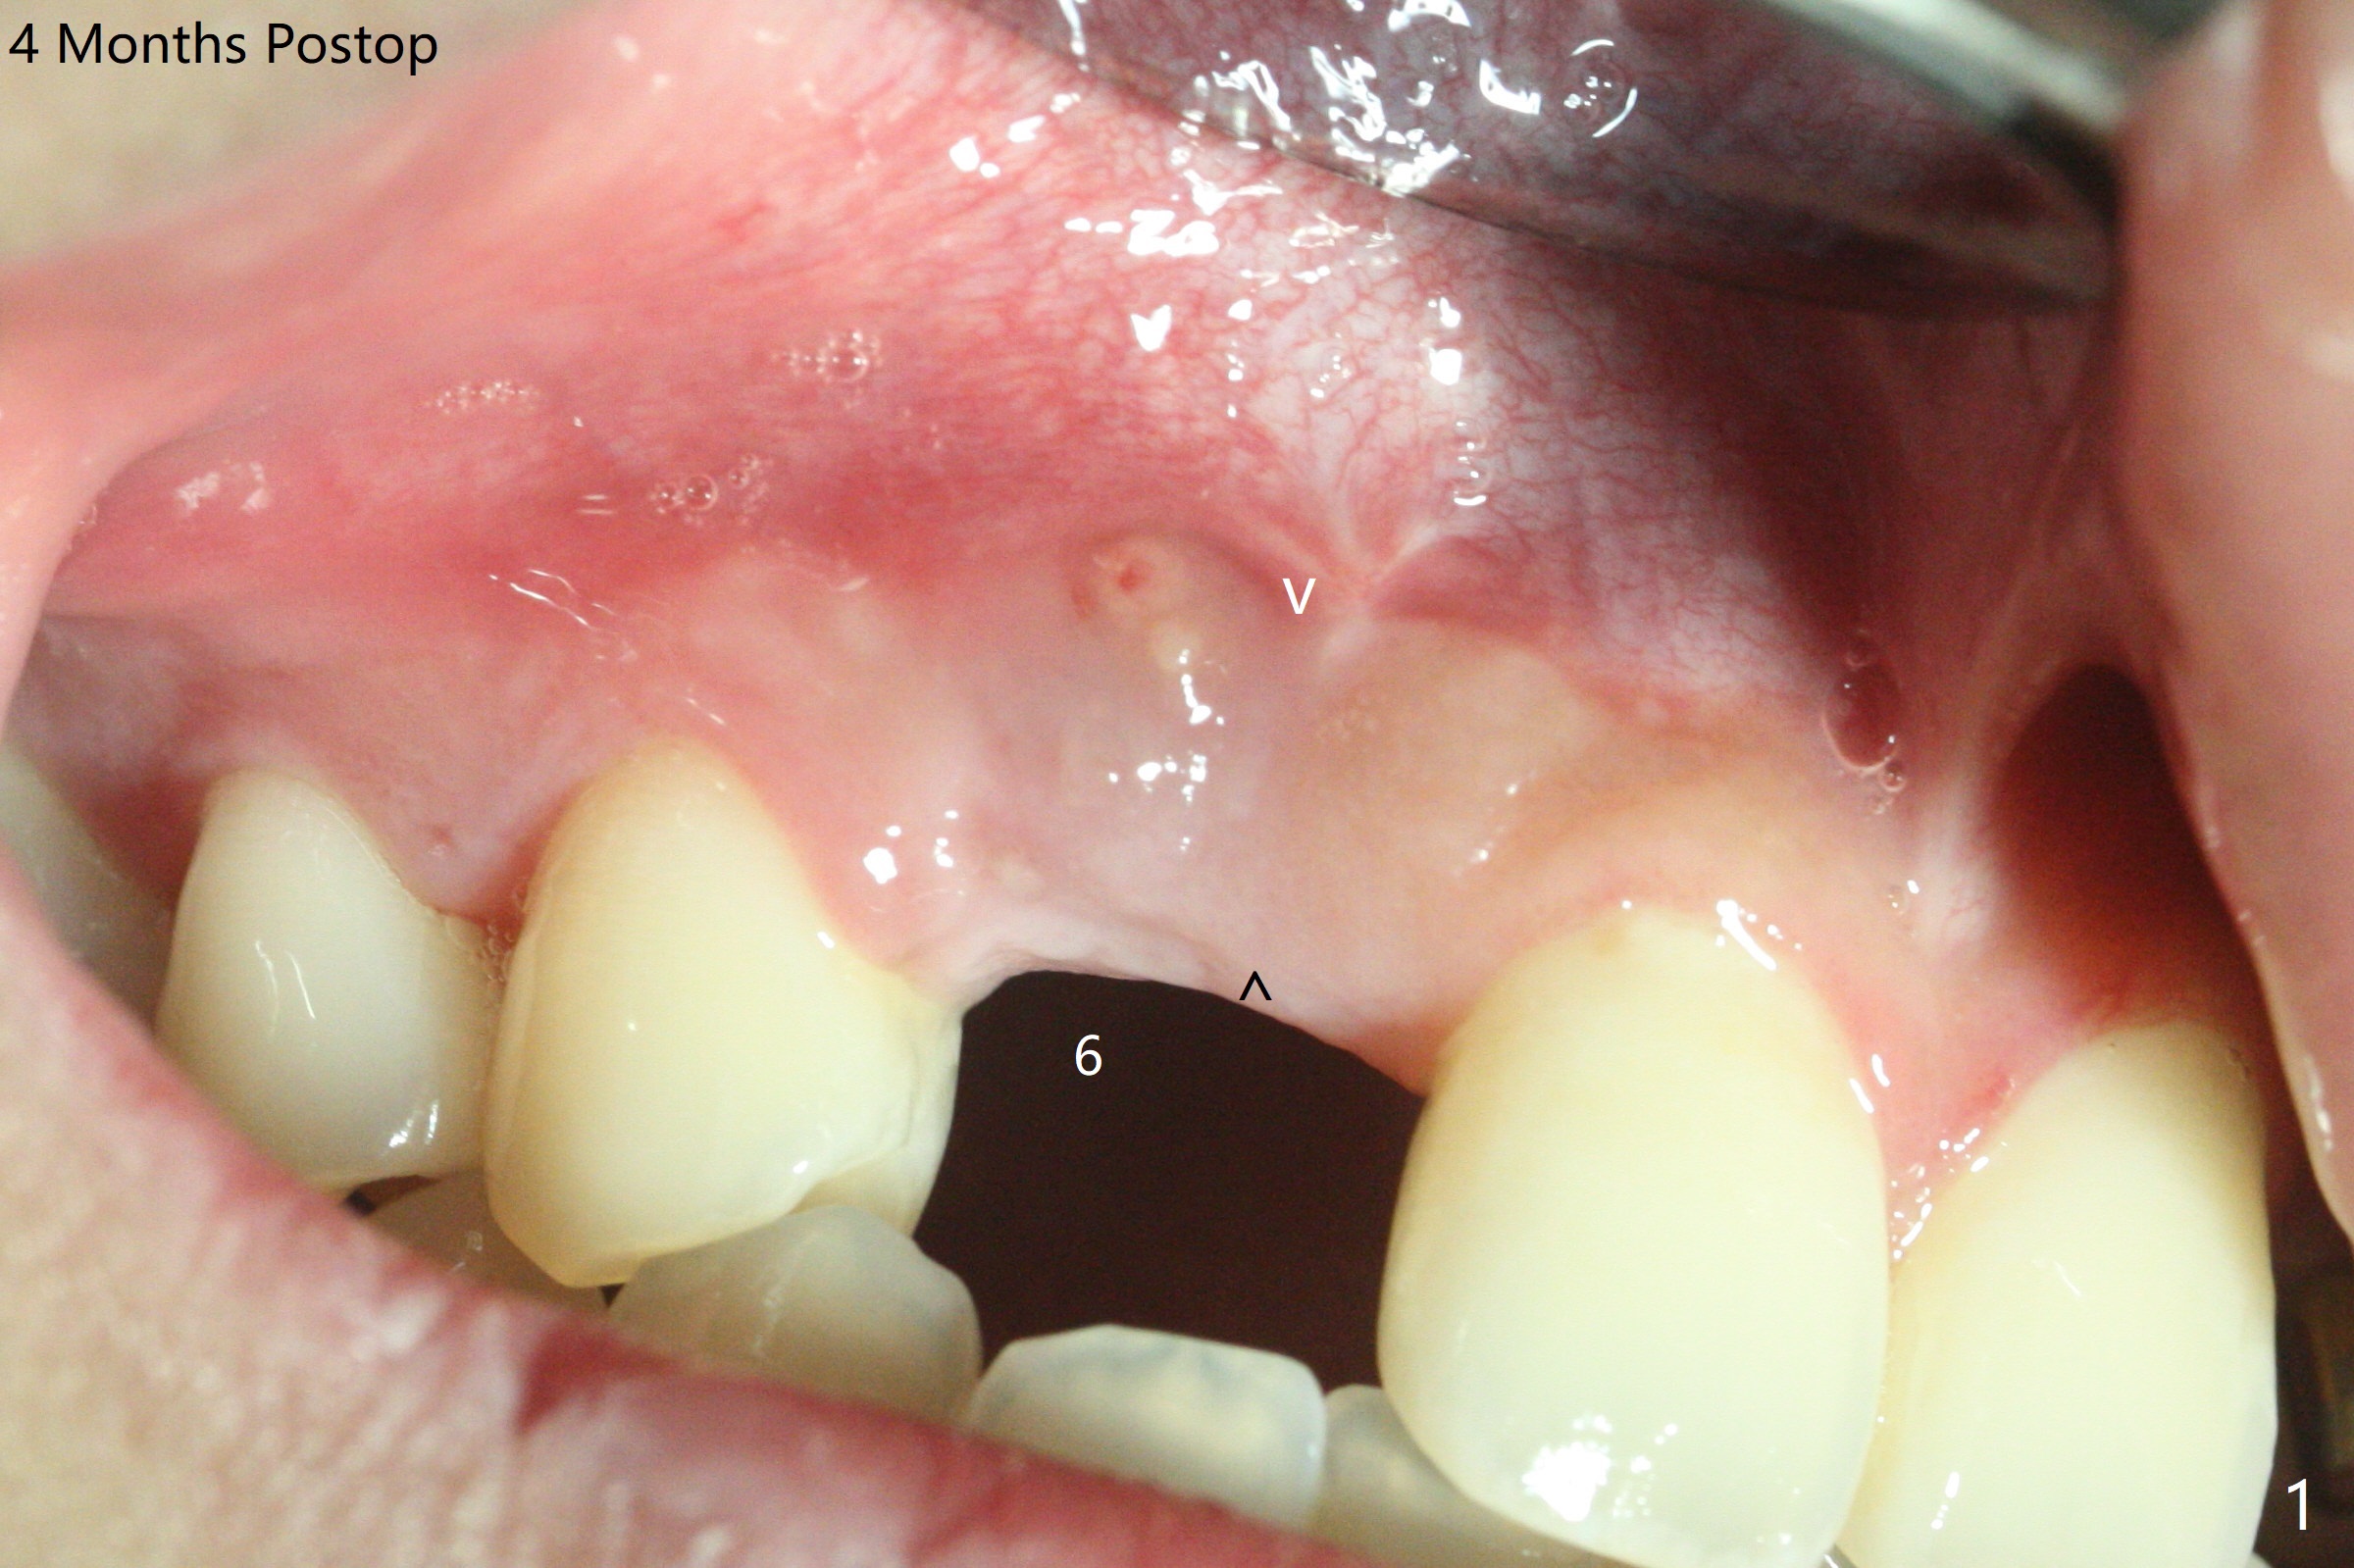

18岁男从外州大学回来,无症状,但是6号牙(右上尖牙)颊侧瘘道(图一,二(角化龈充分(箭头))),根尖片显示植体近中骨吸收(图三:*),而对侧植体仿佛骨整合(图四)。患侧切开后发现植体颊侧暴露,松动。拔除后骨缺损由粘性骨粉修复(图七,九:*),覆盖PRF膜(图七:P)和带钛网(图九:^)不可吸收膜(图五-七),后者用两个小钉子固定(图六(腭侧),七(颊侧),九),使用新的刀片和一个特殊尖头剥离器在颊侧骨膜下相当广泛分离,使用PTFE缝线,粘膜下水平褥式缝合之后(图八:箭头),多个垂直间断缝合,两个乳头垂直褥式缝合。术后一周伤口没有裂开,术后疼痛肿胀已经消退(图十)。术后十八天牙槽嵴仿佛比对侧还要宽(图十一,三与图十二,四(取模)对比)。术后5.5个月伤口没有裂开,牙槽骨,角化龈宽(图十六),与钛网和两个小钉子固定有关(图十五,十七)。CT显示牙槽骨只能容纳2.5或者3.0毫米植体(图十八)。11号牙植体牙冠粘固后没有骨质吸收(图十九),其实10,11号牙颊侧骨板隆起(图二十至二十二),而6植体失败,颊侧骨板吸收,甚至累及5号牙(图十七)。